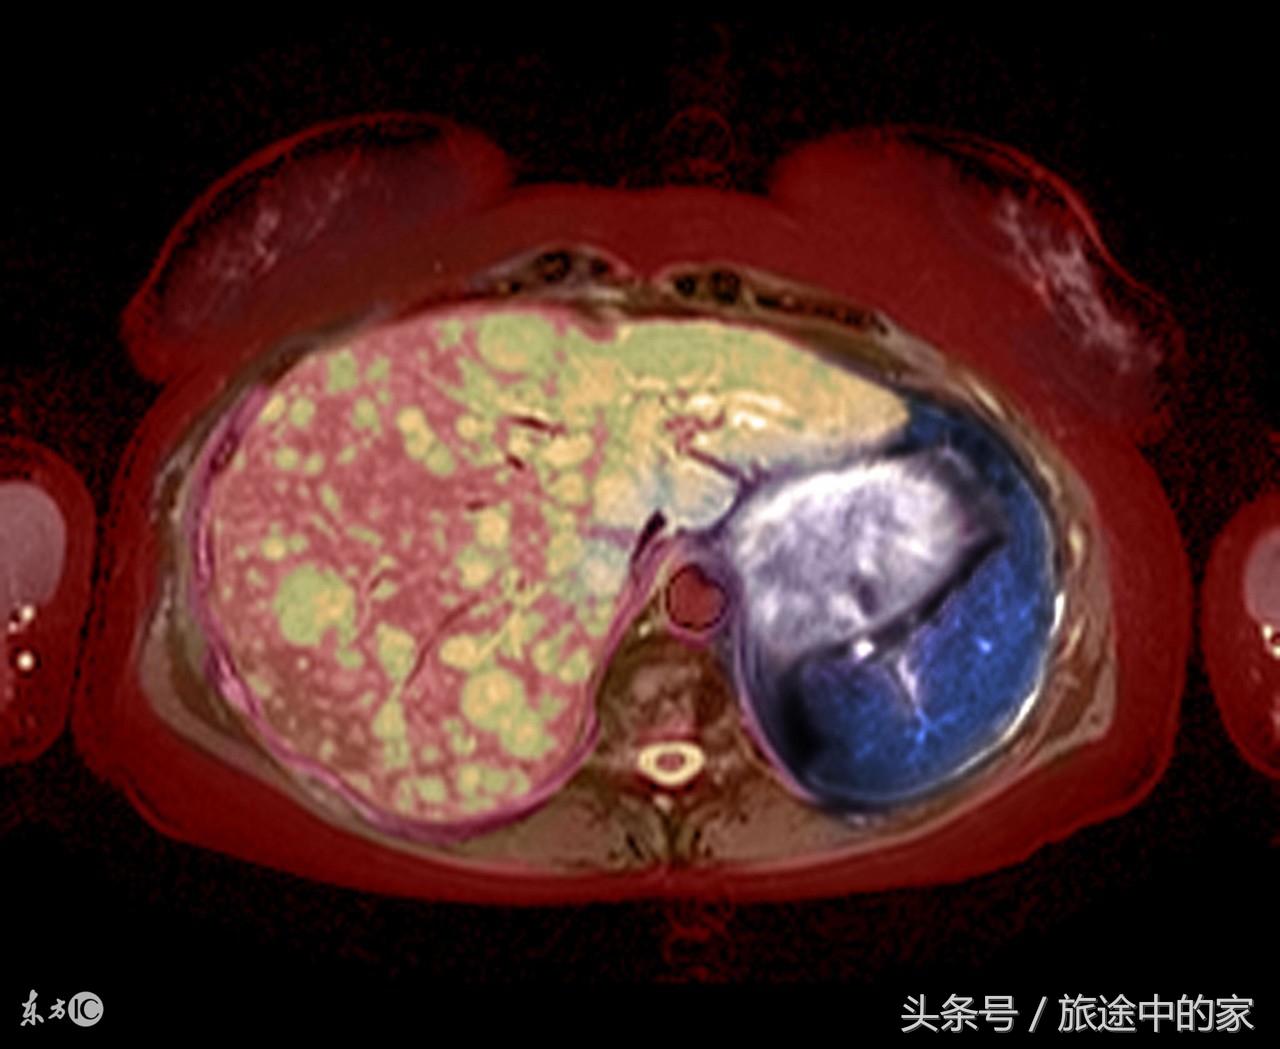

9)肝癌:肝癌对的早期发现很重要,因为肝癌起病隐匿,发展迅速,治疗困难,预后也不好,所以很多肿瘤专家将肝癌称之为“癌中之王”。肝癌早期症状如下:肝区持续性疼痛,痛感为钝痛;食欲下降,容易疲乏,无精打采;腹部闷胀、腹泻、体重下降、越来越消瘦;皮肤和眼球发黄,尿色变黄,且随着时间逐渐加重,这些早期症状与慢性肝炎和肝硬化相似,所以极容易混淆。